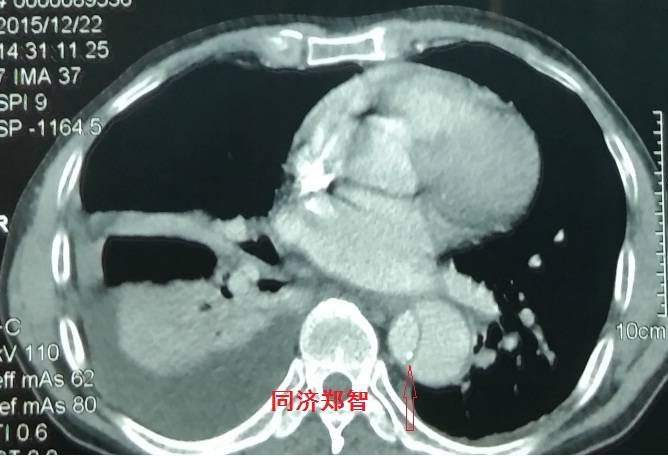

病例四

腹部平扫CT提示腹主动脉增宽,CTA证实为腹主动脉局限性夹层(红箭头所示)